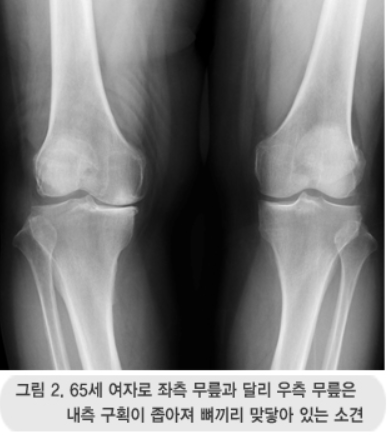

특히 무릎 모양이 휘어져 걷기가 불편하거나, 다리가 굳어져 정상적인 보행이 어려운 경우에 수술이 고려됩니다. 대한정형외과학회에서는 수술 결정을 위해 다음과 같은 6가지 요소를 종합적으로 평가할 것을 권장하고 있어요.

- 엑스레이 등 방사선 소견

예를 들어, 방사선 사진상 관절염이 많이 진행됐더라도 평소 통증이 경미하거나 약물치료로 조절된다면 수술은 권장되지 않아요. 또한, 쪼그려 앉을 때만 불편한 경우도 수술 대상에서 제외되는 편이에요.